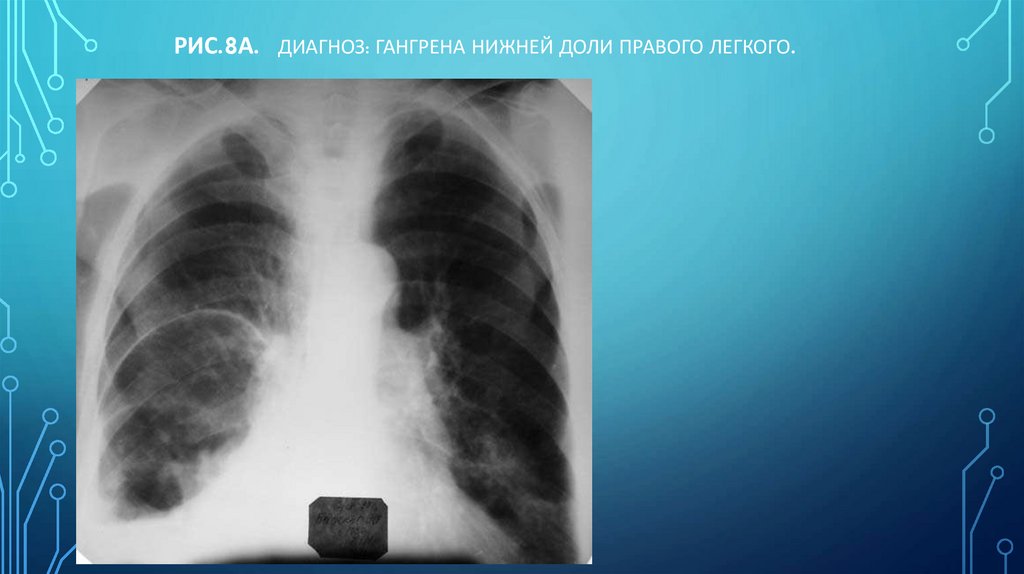

Рис.8а. Диагноз: Гангрена нижней доли правого легкого.

117. Рис.8а. Диагноз: Гангрена нижней доли правого легкого.

Н.С. ВОРОТЫНЦЕВА, С.С. ГОЛЬЕВ РЕНТГЕНОПУЛЬМОНОЛОГИЯ